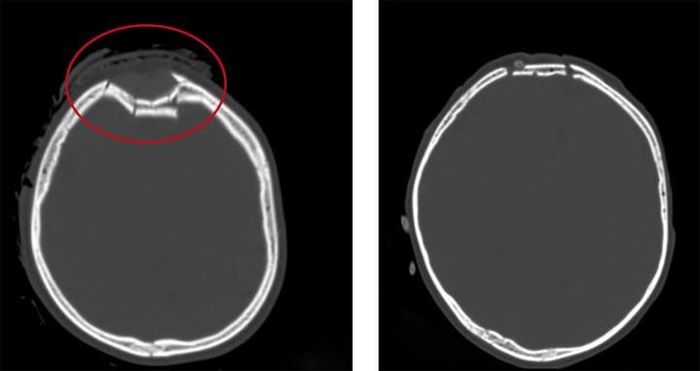

Hình ảnh vùng sọ não bị lún của trẻ trước và sau khi phẫu thuật (vùng khoanh tròn màu đỏ). (Ảnh: Bệnh viện Việt Nam - Thụy Điển Uông Bí)

Các bác sĩ khi thăm khám trên phim chụp CT.Scanner sọ não phát hiện, trẻ bị vỡ lún xương sọ trán phải, đụng dập tụ máu nhu mô não trán phải. Bệnh nhi được phẫu thuật nâng lún xương sọ, cầm máu và xử trí vết thương.